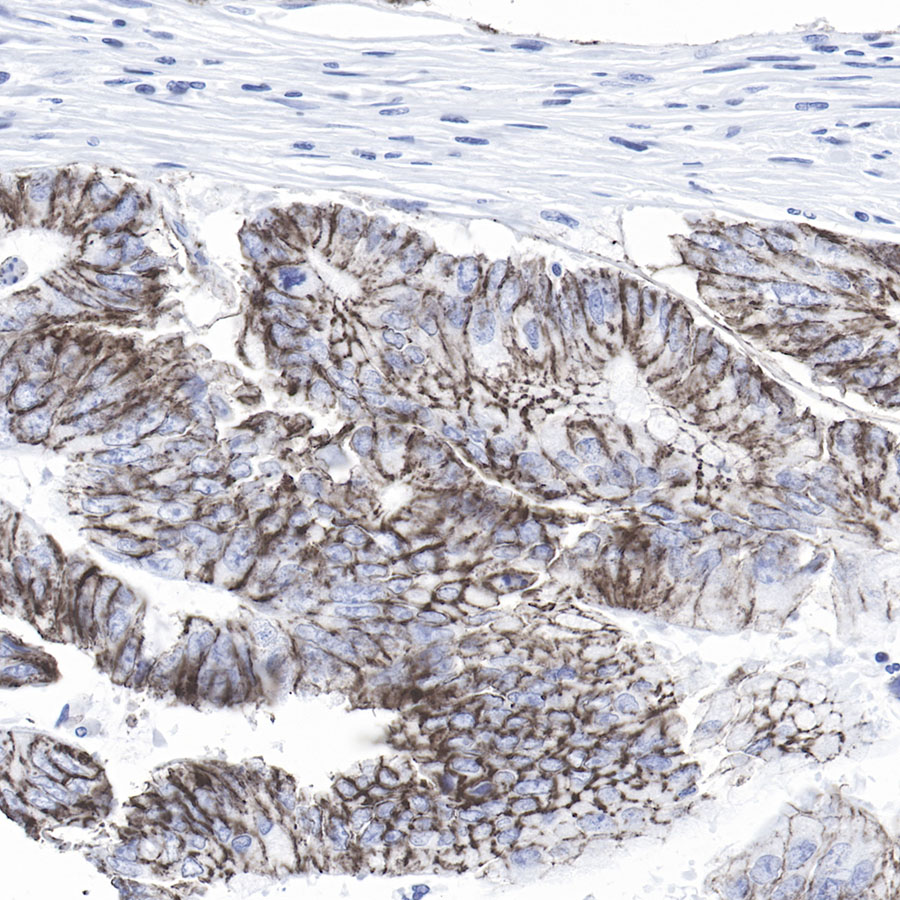

免疫组化

IHC shows positive staining in paraffin-embedded human colon cancer.

Anti-Claudin-1 antibody was used at 1/500 dilution, followed by a Goat Anti-Rabbit IgG H&L (HRP) ready to use. Counterstained with hematoxylin.

Heat mediated antigen retrieval with Tris/EDTA buffer pH9.0 was performed before commencing with IHC staining protocol.